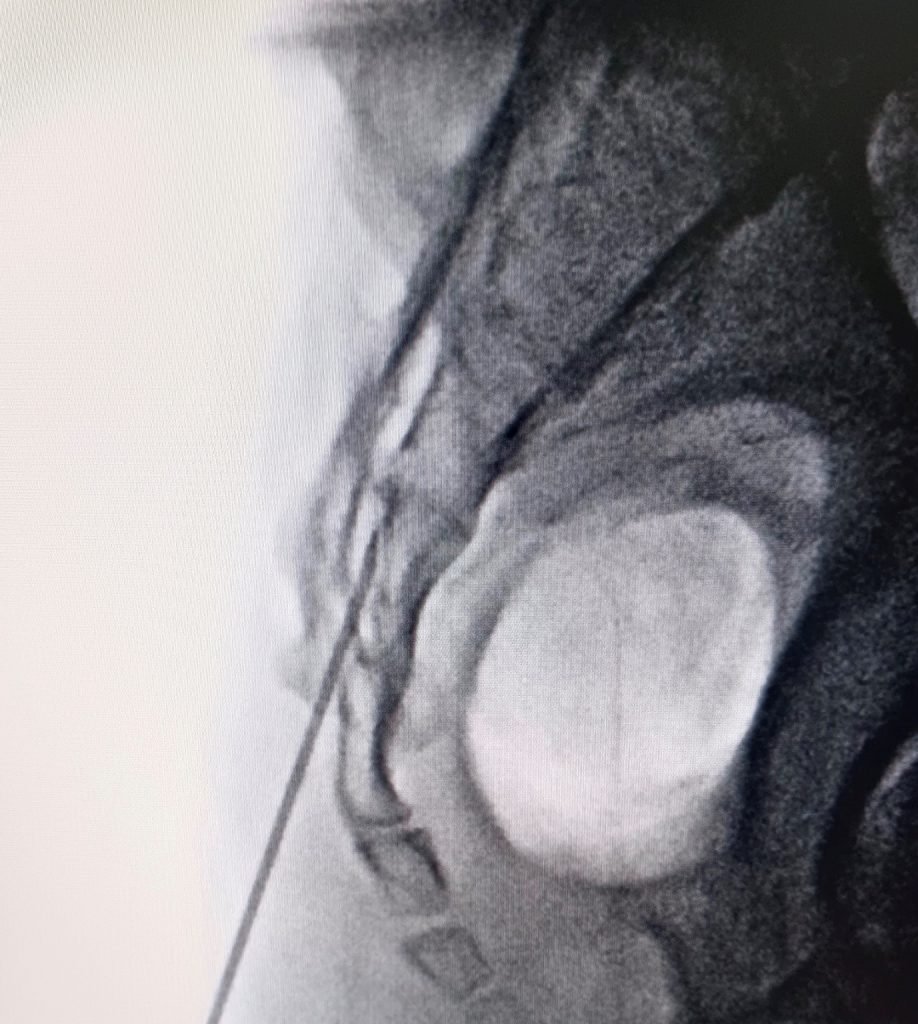

Non-Surgical Disc Prolapse Pain Management

Advanced Slip Disc Treatment by Dr. Nitish Agrawal – Best Spine Surgeon in Pune

Non-Surgical Disc Prolapse Pain Management refers to conservative treatment methods used to relieve pain caused by a disc prolapse (slip disc) without the need for surgery. In this condition, the bulging or herniated disc presses on nearby nerves, leading to back pain, leg pain (sciatica), numbness, or tingling. Many patients experience significant relief with well-planned non-operative treatment.

- Selective Nerve Root Block for targeted pain relief

- Caudal Epidural Steroid Injection to reduce nerve inflammation